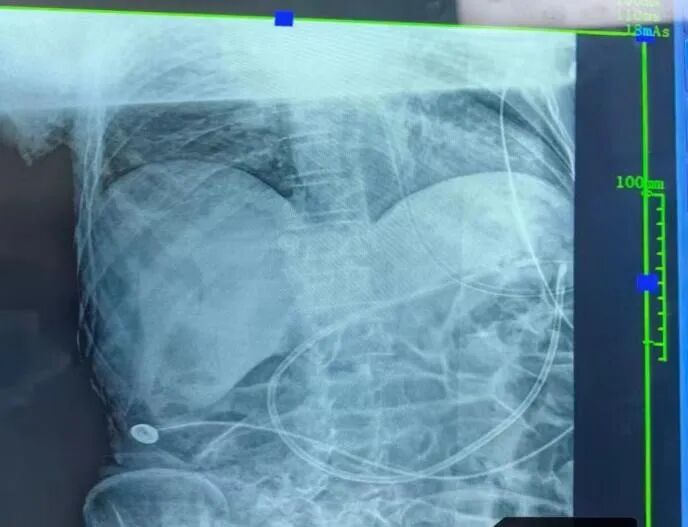

以67岁的谭先生为例,因急性呼吸衰竭合并吸入性肺炎转入ICU,伴有严重胃潴留,传统鼻胃管喂养难以实施,导致感染控制不佳。ICU团队在床旁超声实时引导下,成功将鼻肠管置入空肠,实现幽门后喂养。治疗后,患者炎症指标明显下降,营养状态逐步改善,为脱离呼吸机及后续康复创造了条件,目前已顺利转入普通病房。

幽门后喂养是指将营养液通过鼻肠管直接输送至十二指肠或空肠,绕过胃部进行肠内营养支持。该技术能有效减少反流与误吸风险,降低肺部感染发生率,尤其适用于胃排空障碍、重症胰腺炎、长期卧床且需营养支持的患者。